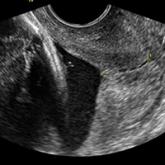

ArticleUniversal cervical length screening–saving babies livesAuthor:Rupsa C. Boelig, MDPublish date: May 30, 2017Universal second-trimester transvaginal ultrasound cervical length screening of both singleton and twin gestations should be seriously considered b...Read More